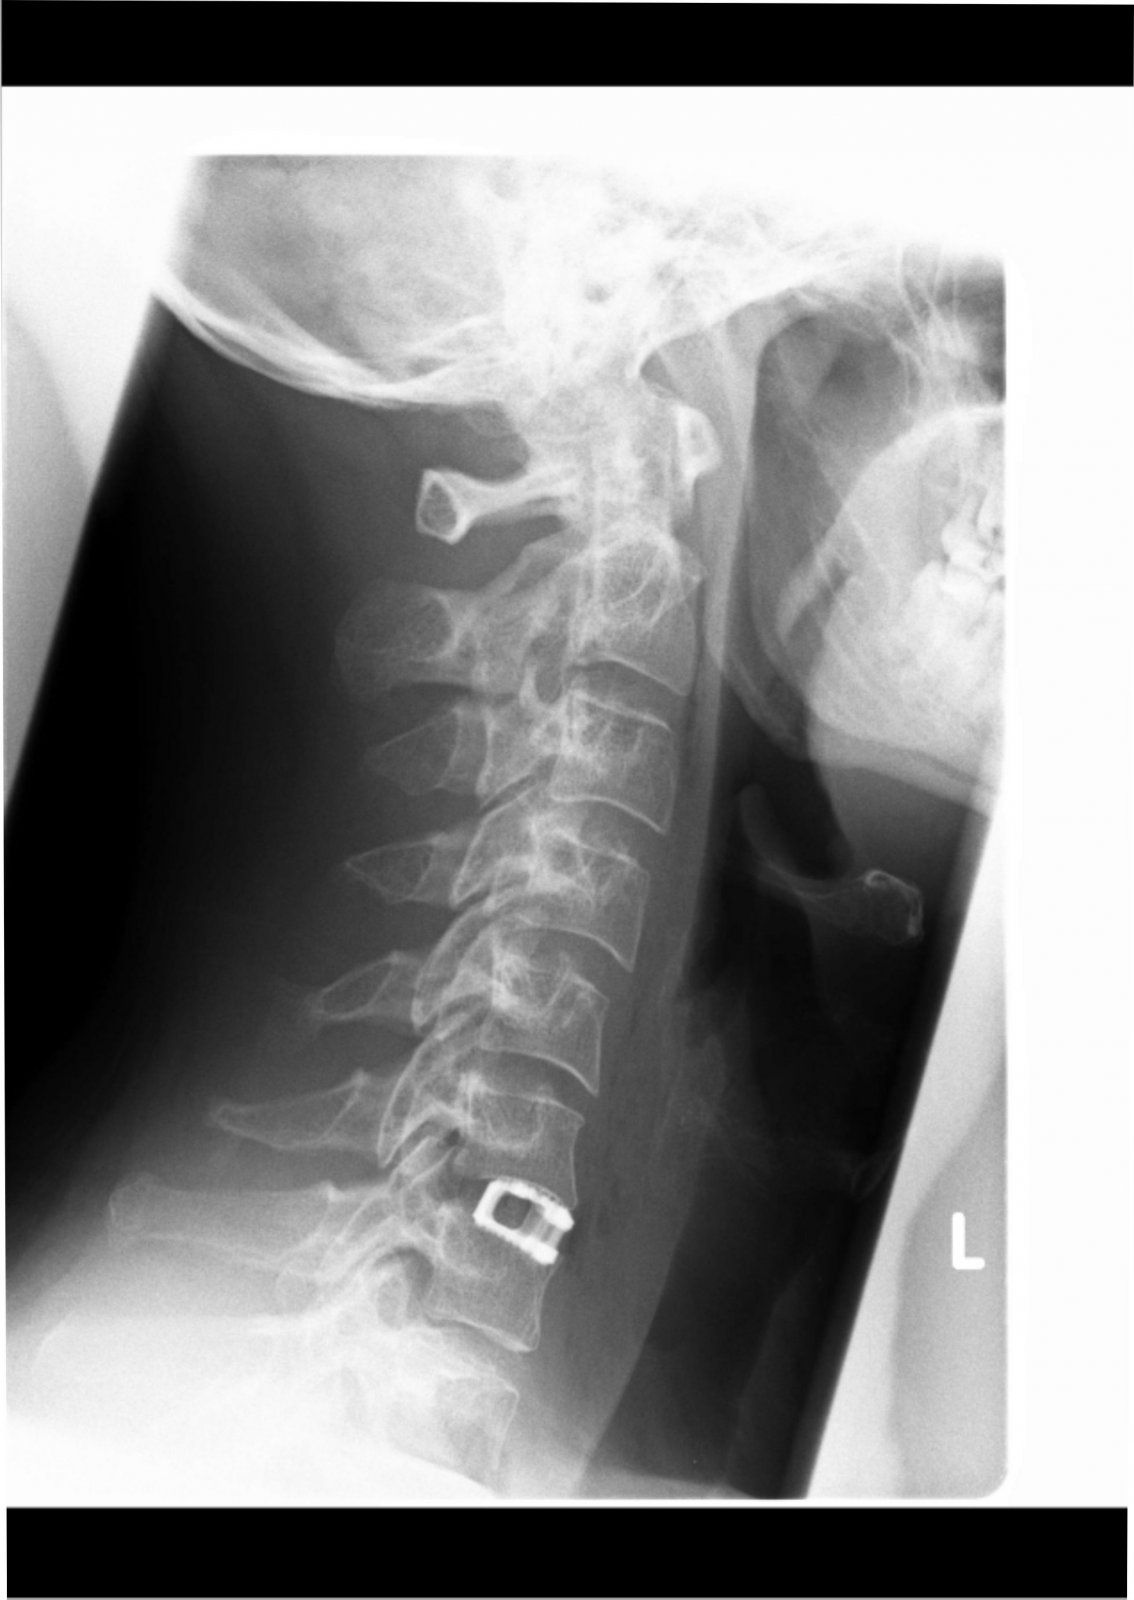

Zack, zu kurz und Schulterblatt gebrochen….